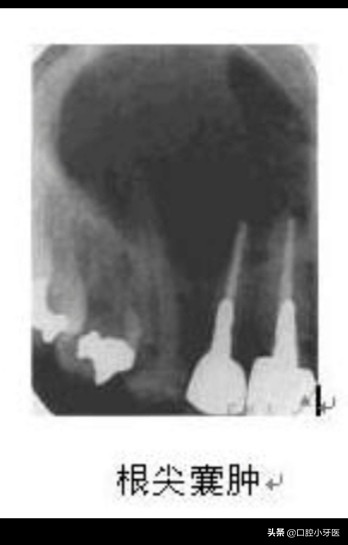

如果这两种情况没有及时的处理,那么将会发生比较严重的根尖周囊肿,根尖周囊肿是这三种情况当中最严重的,可能的原因是由于根尖周肉芽肿中心部位的血运不够,中心发生化脓液化变大,变成根尖周囊肿,根尖周囊肿体积较大对颌骨造成破坏,在影像学上显示出低密度的影像,边缘界限清晰!